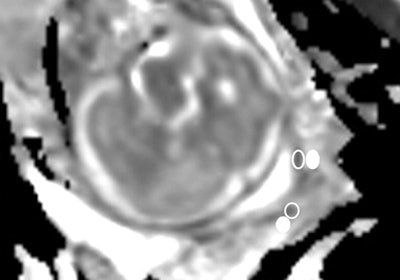

Images are from a 28-year-old woman at 30 weeks of gestation with a sonographic cervical length of 8 mm who was referred for suspected corpus callosum dysgenesis. MRI (left) shows a short cervix with funneling (arrows), with the cervical canal appearing as a zone of high signal intensity. Diffusion-weighted MRI (right) illustrates a uniform hypointense subglandular area of the cervix without any restriction of diffusion.

The ADC map gives a value of 2,681 x 10-6 mm2/sec in the subglandular area (empty oval). The patient gave birth four days later. Images courtesy of Radiology.The researchers found no difference in cervical length on ultrasound between the two patient groups. ADC values in the outer cervical stroma were also similar between the groups.